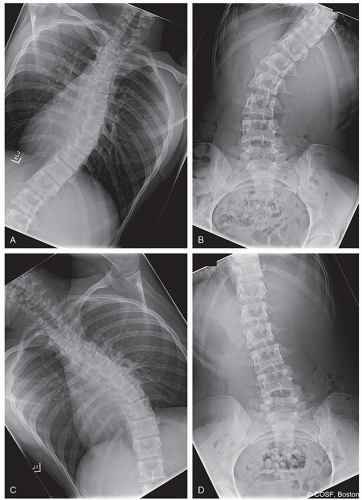

Right and left bending films to adequately determine flexibility and Lenke criteria (Figure 3.2)

Atypical curves: Left thoracic, kyphosis, severe coronal decompensation